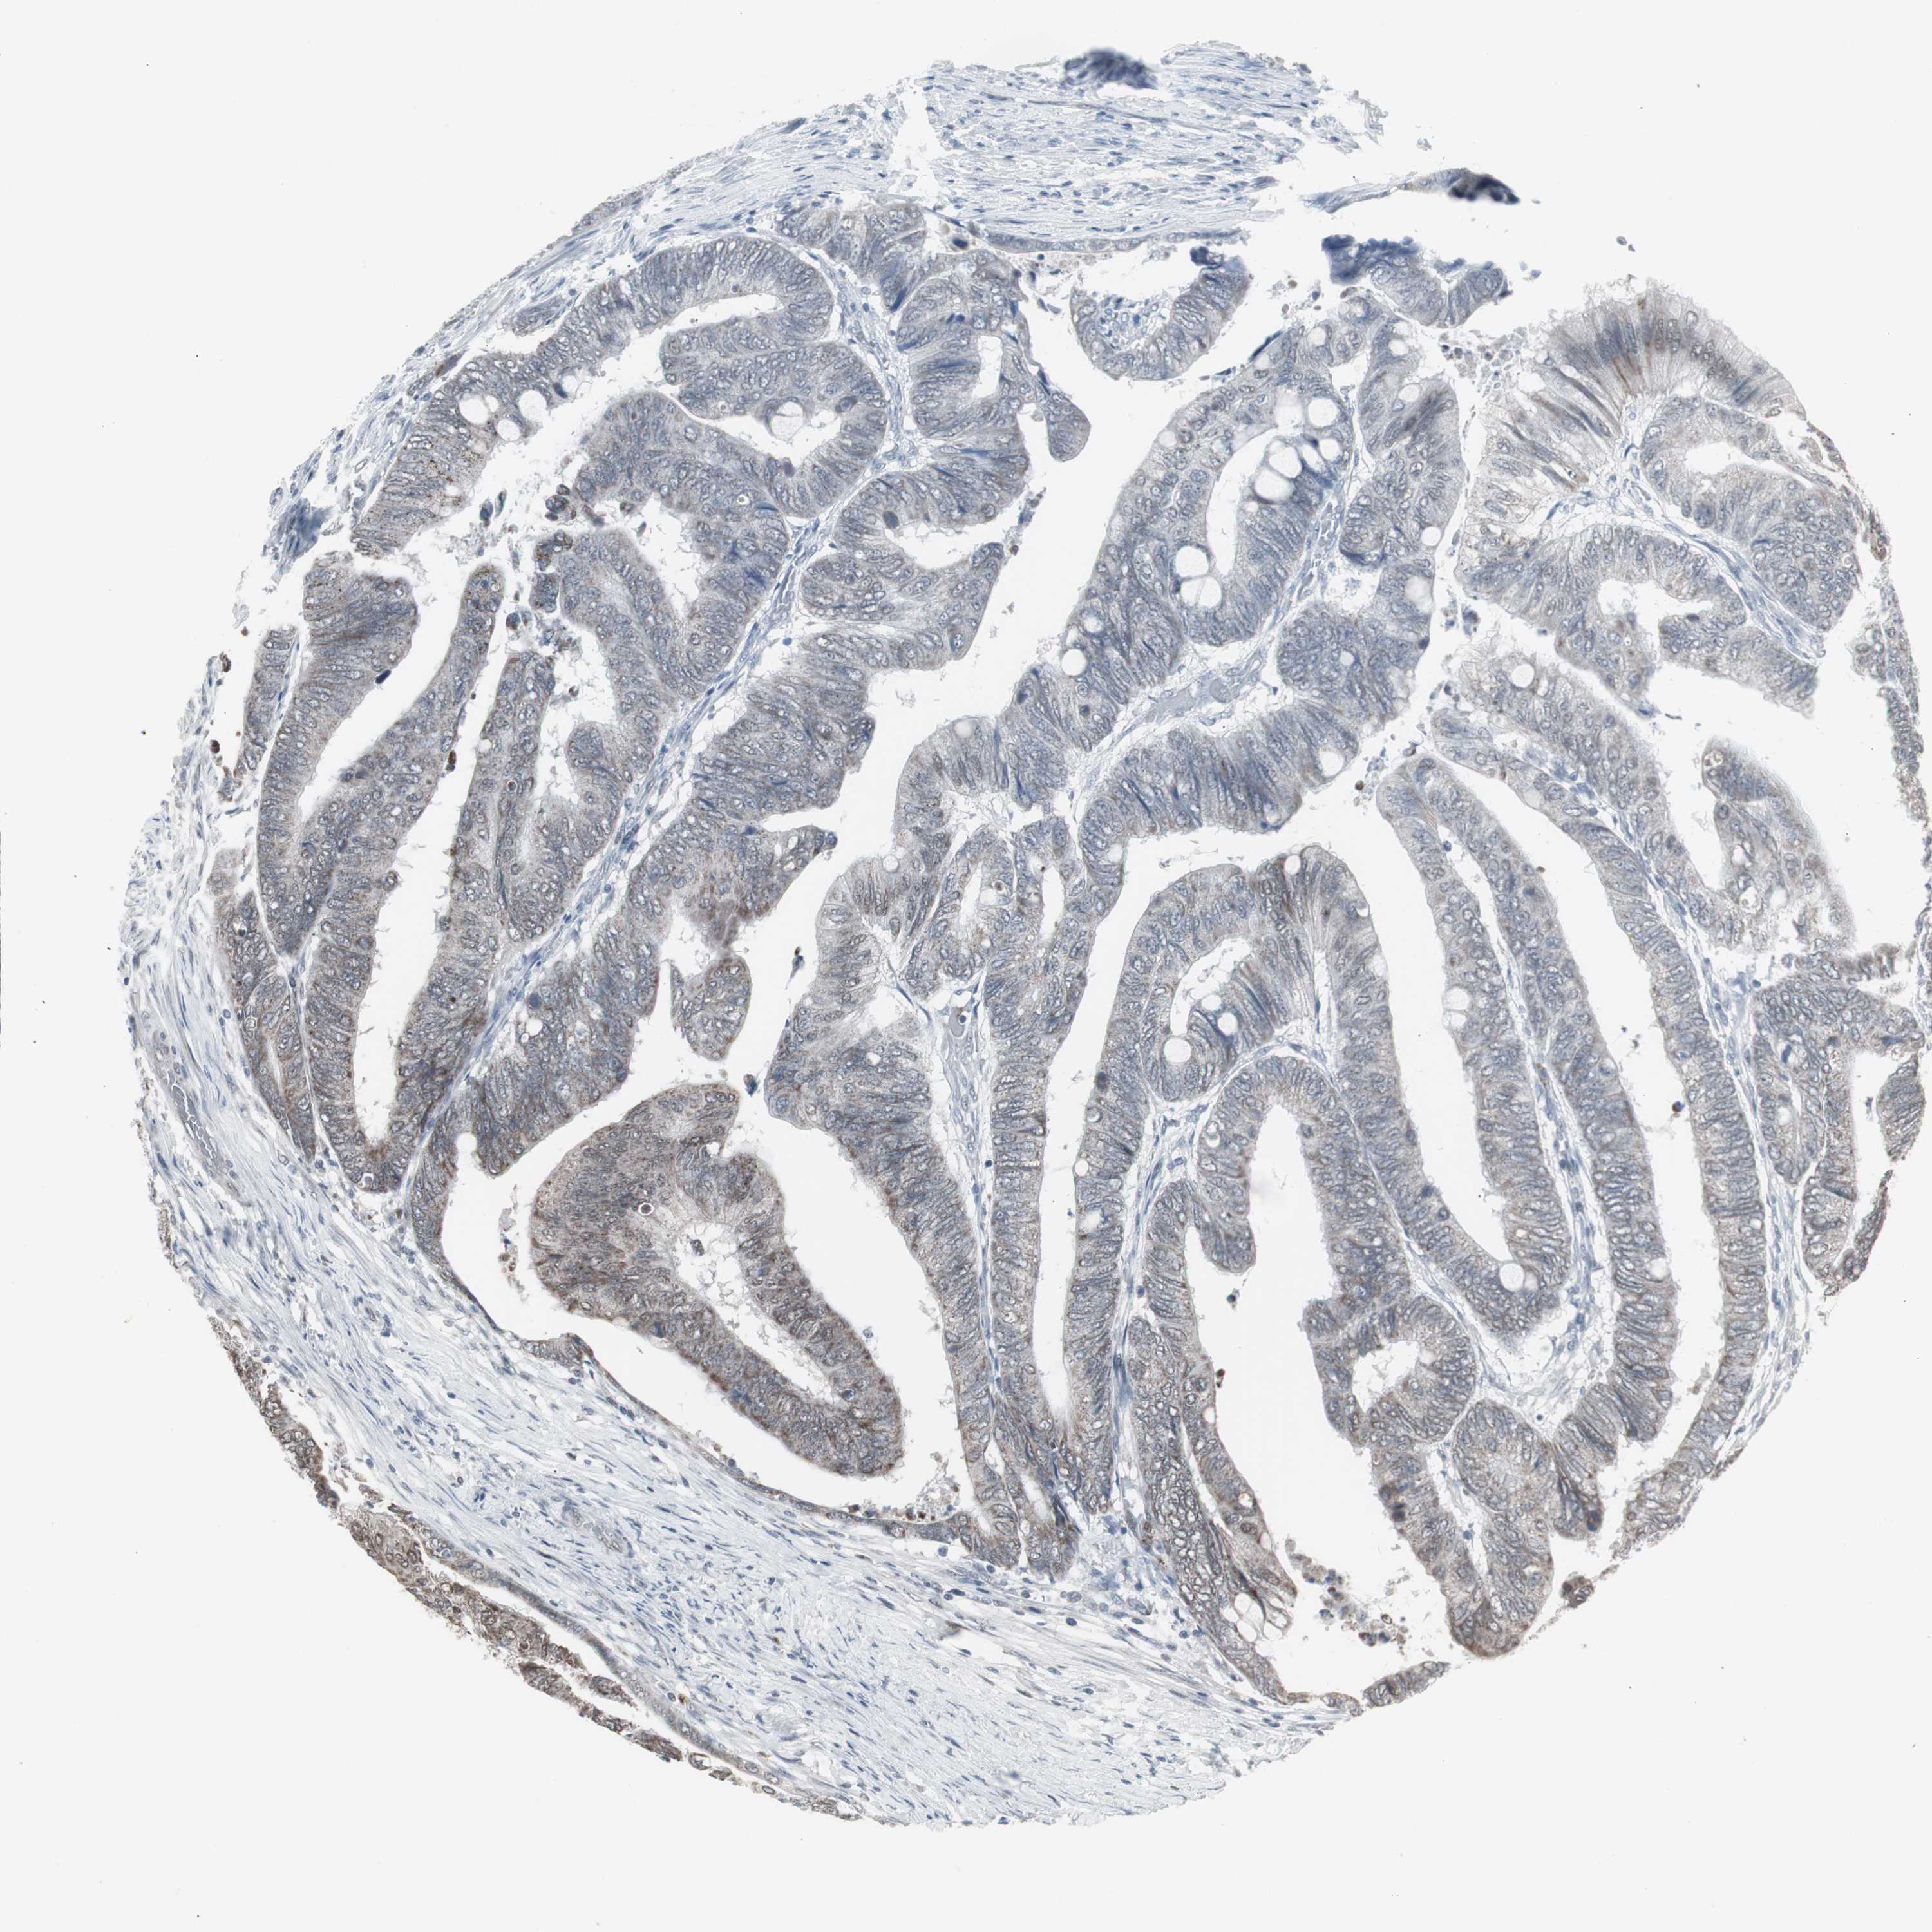

RECTUM ADENOCARCINOMA (TCGA) - Interactive survival scatter ploti

RXRA is not prognostic in Rectum Adenocarcinoma (TCGA)

TCGA RNA samplesi

Average pTPM 18.4

Number of samples 88